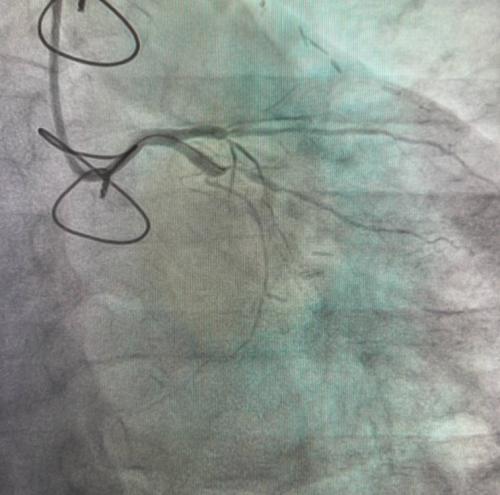

После госпитализации и обследования кардиологи диагностировали сложное атеросклеротическое поражение огибающей артерии с полным ее закрытием.

Для восстановления кровотока врачами была выполнена коронарография с последующей установкой стентов с помощью малоинвазивных рентгеноэндоваскулярных технологий.